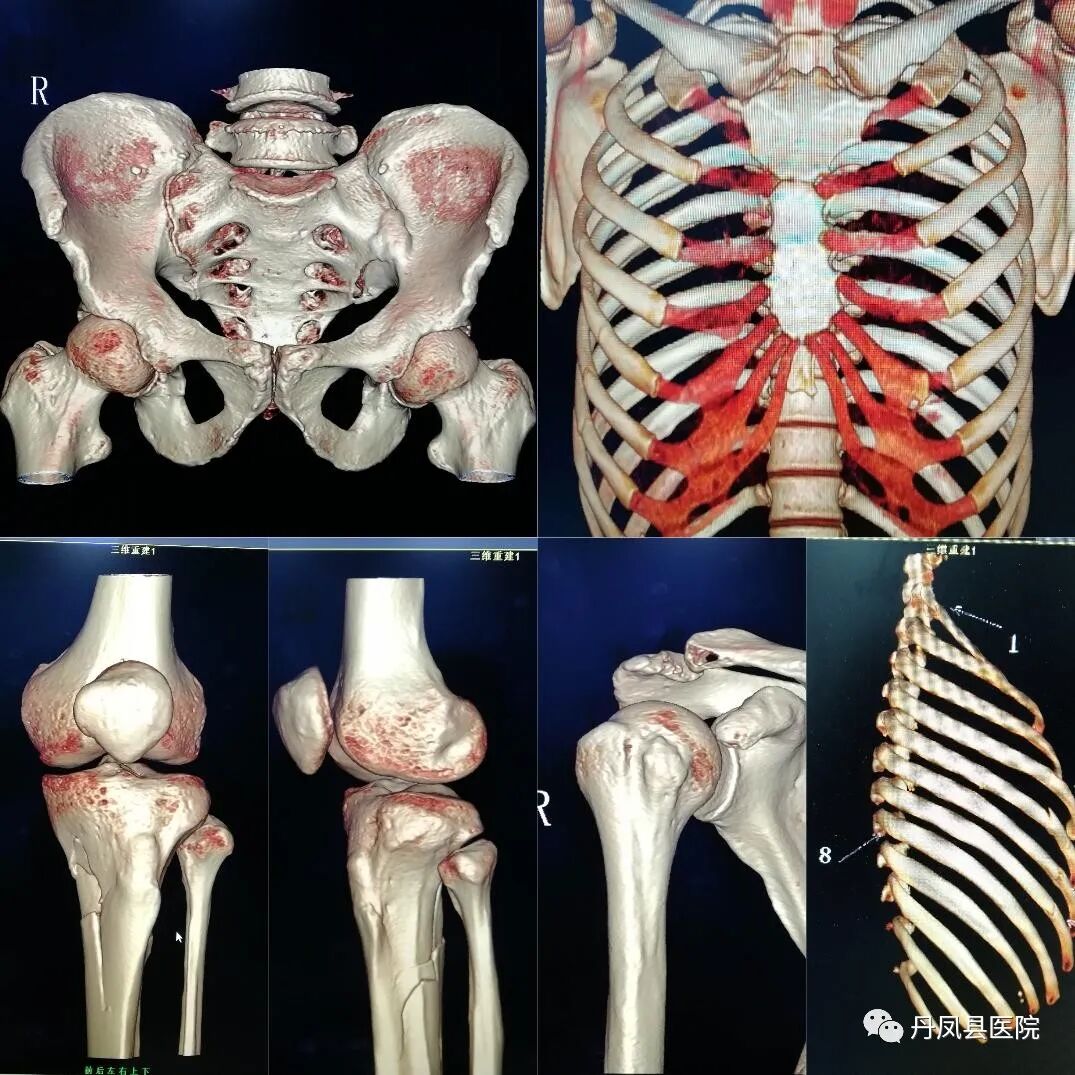

CTCT室目前开展全身各部位常规CT平扫、增强CT扫描、CT血管造影(CTA)、冠状动脉CTA、CT尿路造影(CTU)及骨关节CT三维重建等检查技术。64排128层CT具有扫描速度快、分辨率高、定位准确、低剂量辐射等优势,同时运用强大的后处理工作站进行数据处理、多平面重建,利用PACS网络传输系统与医院HIS系统对接,实时将检查图像、影像诊断结果传输到临床医生工作站终端,满足临床医生和患者的需求。尤其是CT血管造影、冠状动脉CTA检查技术应用的日益成熟,解决了患者三级医院看病难的实际问题,也填补了我县在这方面的空白。

![胸3.png]()

胸部高分辨CT

![]()

骨关节三维成像